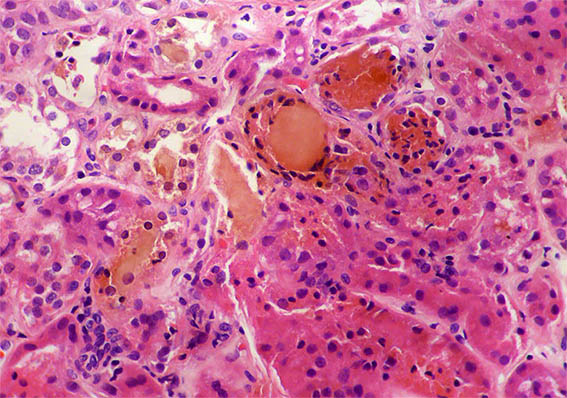

A 40-year-old man presented with severe acute liver failure secondary to hepatitis A virus infection, and acute kidney injury.

More relevant laboratory tests: thrombocytopenia (76,000), hyperbilirubinemia (7.1 mg/dL), transaminitis (1.830 U/L and 2.320 U/L), and elevated INR. Serum creatinine: 5.2 mg/dL, BUN: 78 mg/dL, proteinuria: 100 mg/dL, without microhematuria.

A kidney biopsy was performed. Look at the images.

Figure 2. H&E, X200.

Figure 3.

H&E, X200.